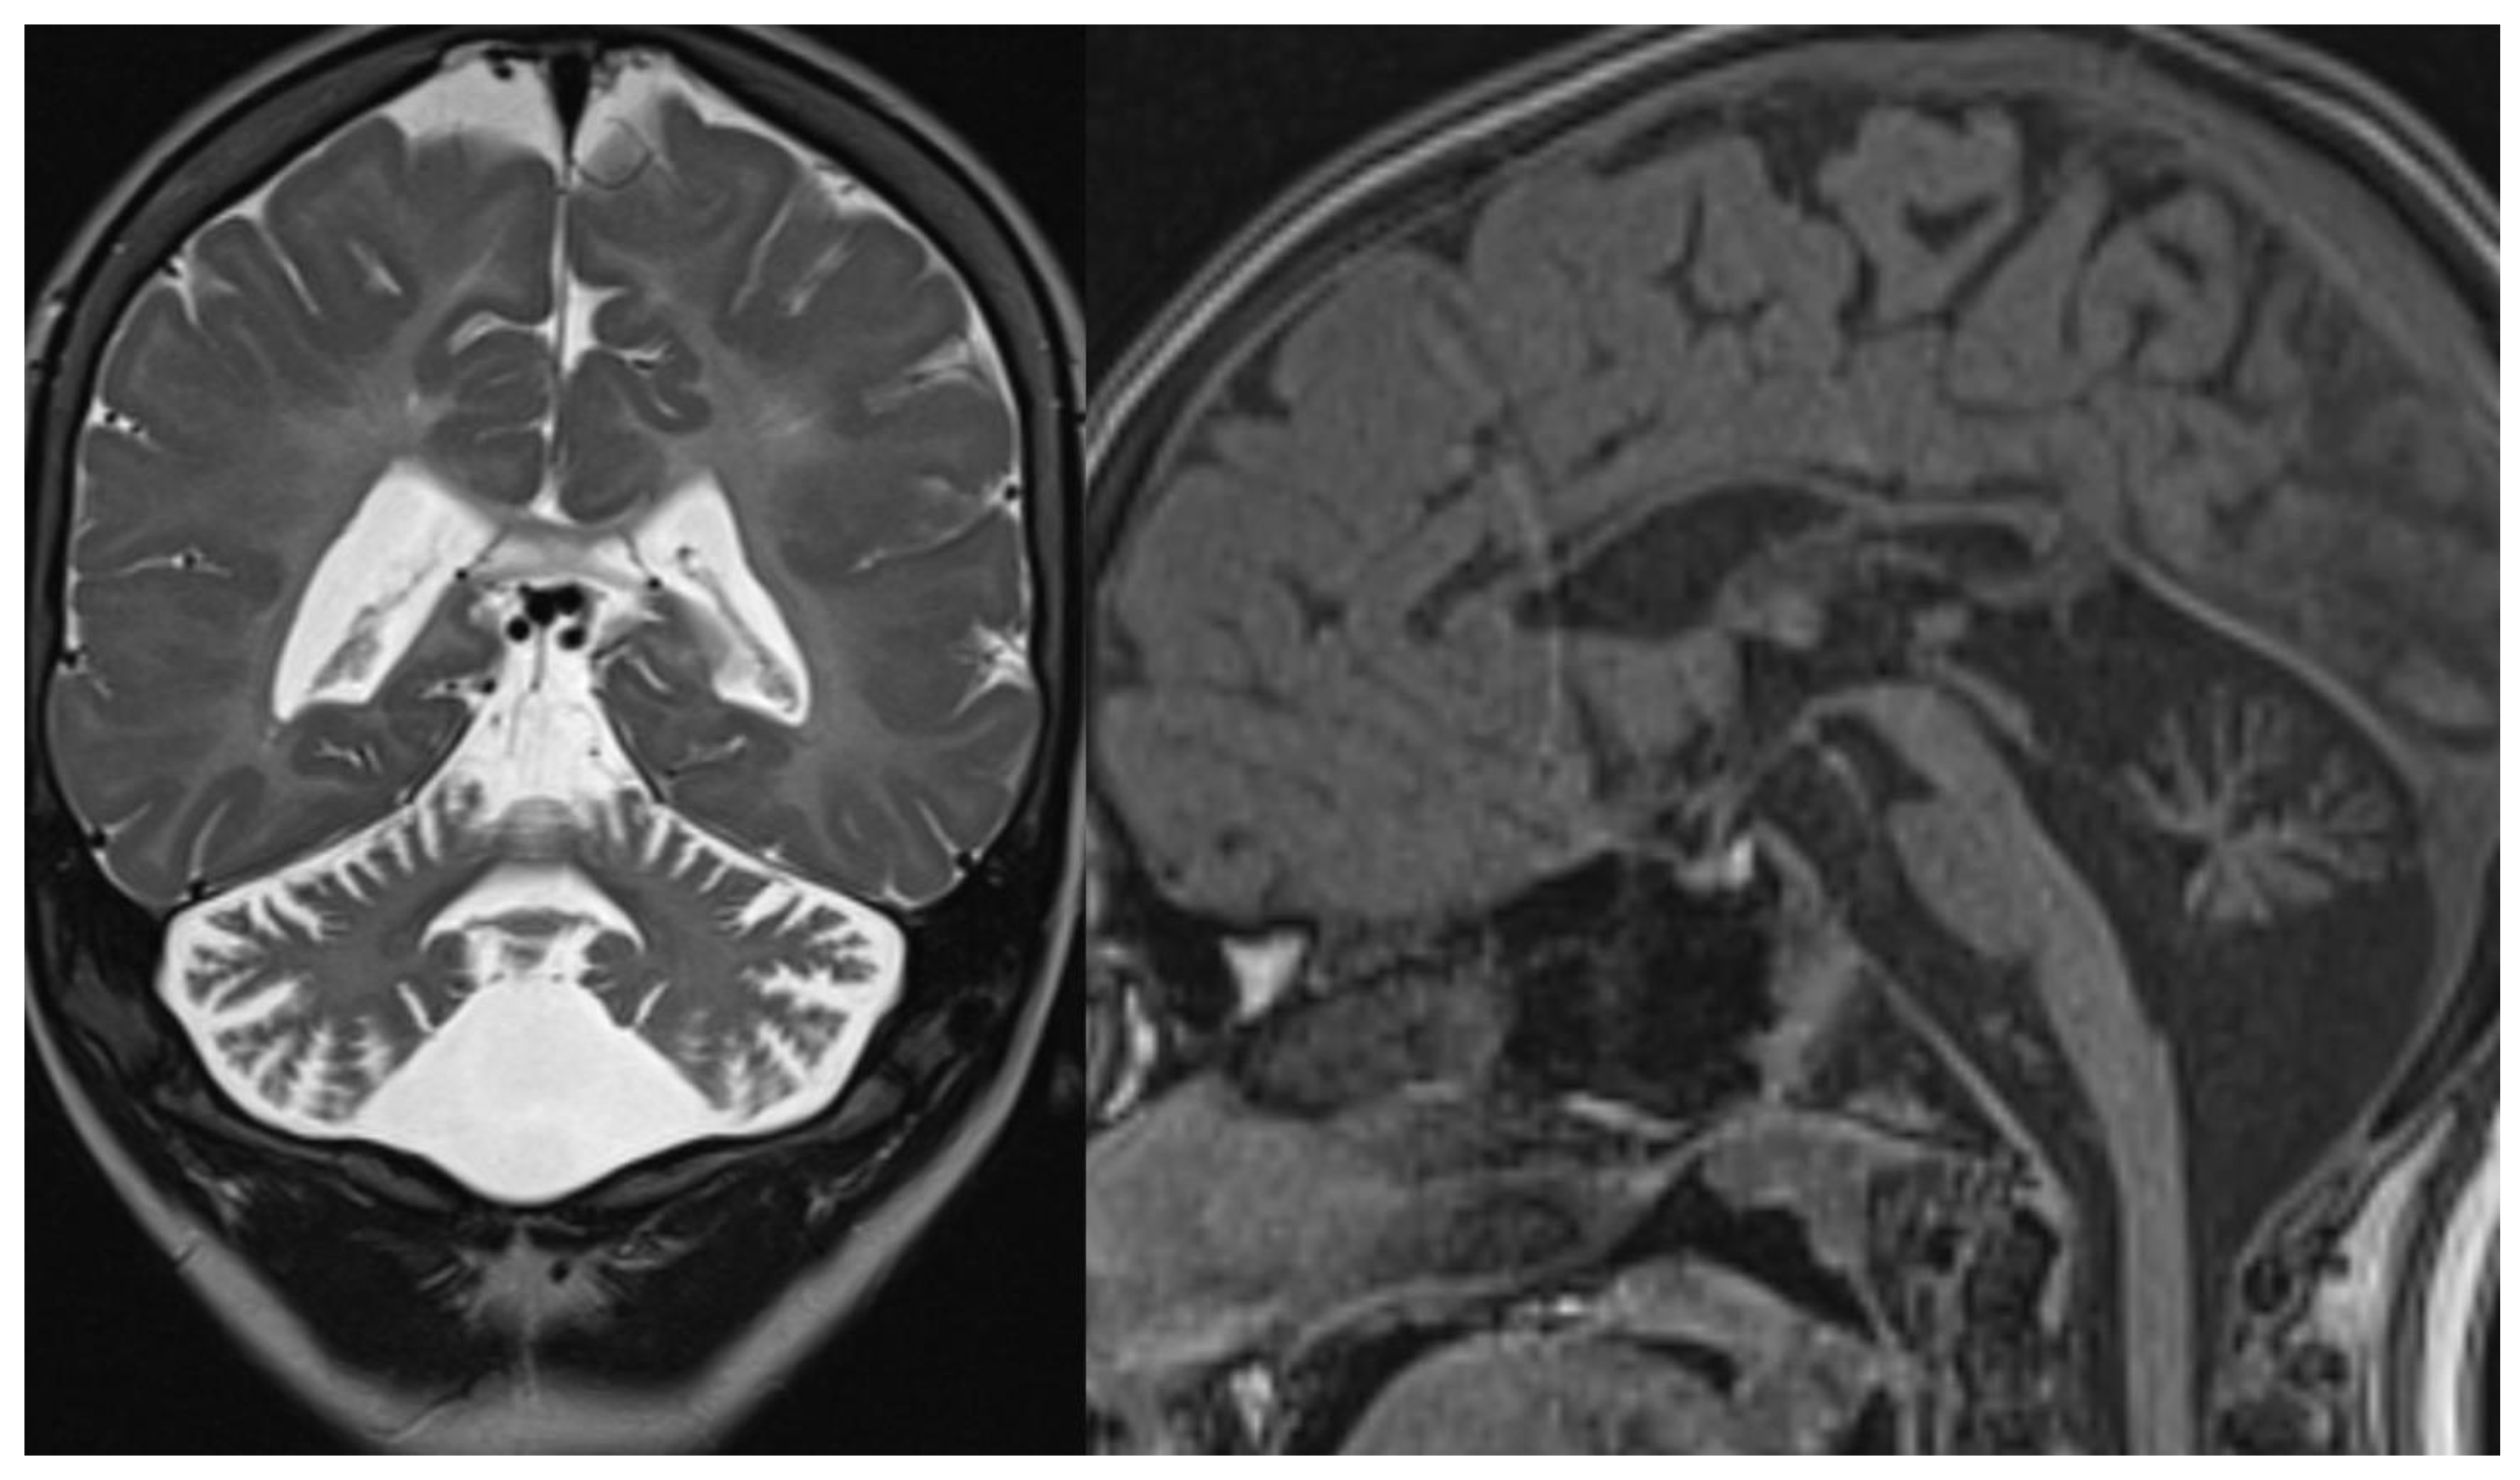

1.8. Ataxia Telangiectasia

Radiological imaging is limited to MRI since CT and studies with x-rays can increase the risk of genetic mutation in these patients highly sensitive to DNA damage by ionizing radiation [

38]. MR images reveal diffuse cerebellar atrophy, with initial involvement of the superior vermis and lateral cerebellar hemispheres and unusual decreased cortical thickness along cerebellar hemispheres. Supratentorial brain shows no sign of volume loss. At the same time, confluent hyperintensities in T2/FLAIR and multiple focal hypointensities (thought to be deposits of haemosiderin related to capillary telangiectasia) are seen in deep white matter, mainly in adult patients [

39]. Hypoplasia of the inferior vermis and a large cisterna magna were also frequent signs [

40] (

Figure 7).

Figure 7.

Ataxia telangiectasia (AT). Brain MRI scan of a 10-year-old girl. MR images reveal severe atrophy of the cerebellar hemispheres, decreased thickness of the cortex of superior cerebellar hemispheres, and hypoplasia of inferior vermis.

Figure 7.

Ataxia telangiectasia (AT). Brain MRI scan of a 10-year-old girl. MR images reveal severe atrophy of the cerebellar hemispheres, decreased thickness of the cortex of superior cerebellar hemispheres, and hypoplasia of inferior vermis.